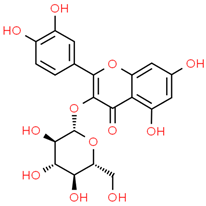

| 8 | Iso-quercetin | 10813969 | C21H20O12 | 464.4 | C1=CC(=C(C=C1C2=C(C(=O)C3=C(C=C(C=C3O2)O)O)OC4C(C(C(C(O4)CO)O)O)O)O)O |  |